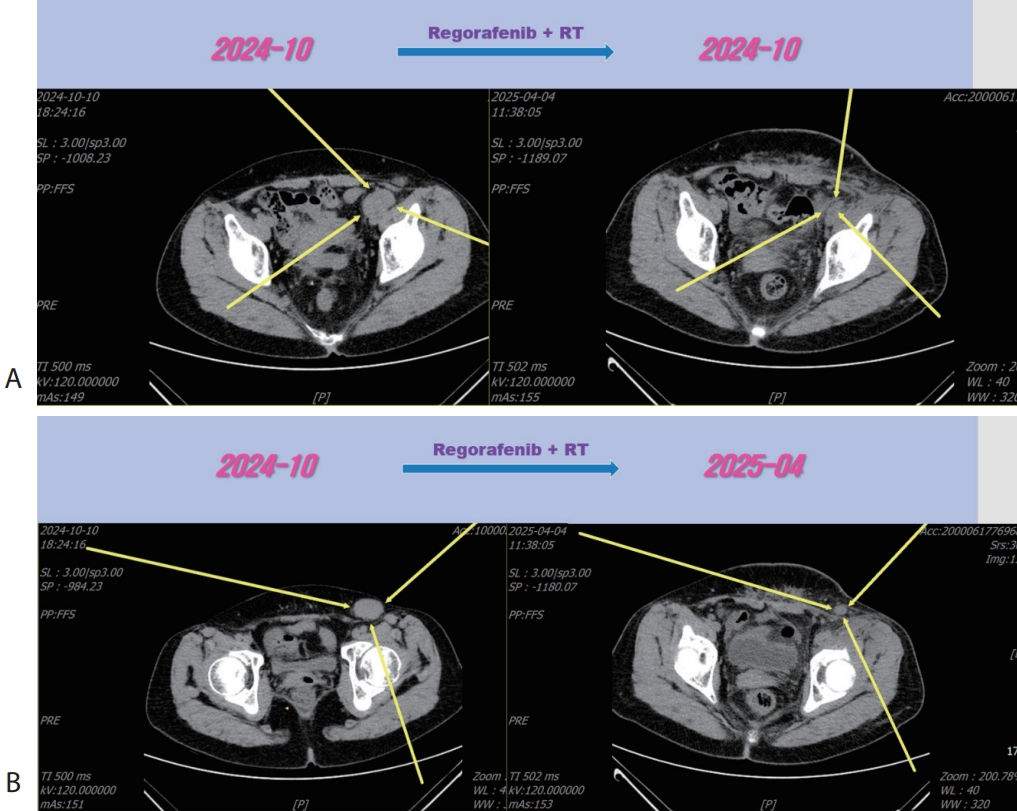

Fig. 4). Then the patient was treated with 3rd line regorafenib (Stivarga

®, 40 mg per dose; Bayer) for 3 months and LN metastasis was slightly increased (

Fig. 5), then we decided to combine RT for LN metastasis (40 Gray/16 fraction). Then the LN metastasis was markedly decreased (

Fig. 6). We are keeping on treating the patient with regorafenib therapy for over 12 months. We summarized treatment timeline of patient (

Figure 5.Liver CT scan (A, B) after 3rd line regorafenib therapy. Pelvic (A) and inguinal (B) lymph node metastasis were slightly increased after regorafenib therapy. CT, computed tomography.

Figure 6.Liver CT scan (A, B) after combination therapy of RT and 3rd line regorafenib. Slightly increasing pelvic (A) and inguinal (B) lymph node metastasis were marked shrinked after combination therapy. CT, computed tomography.